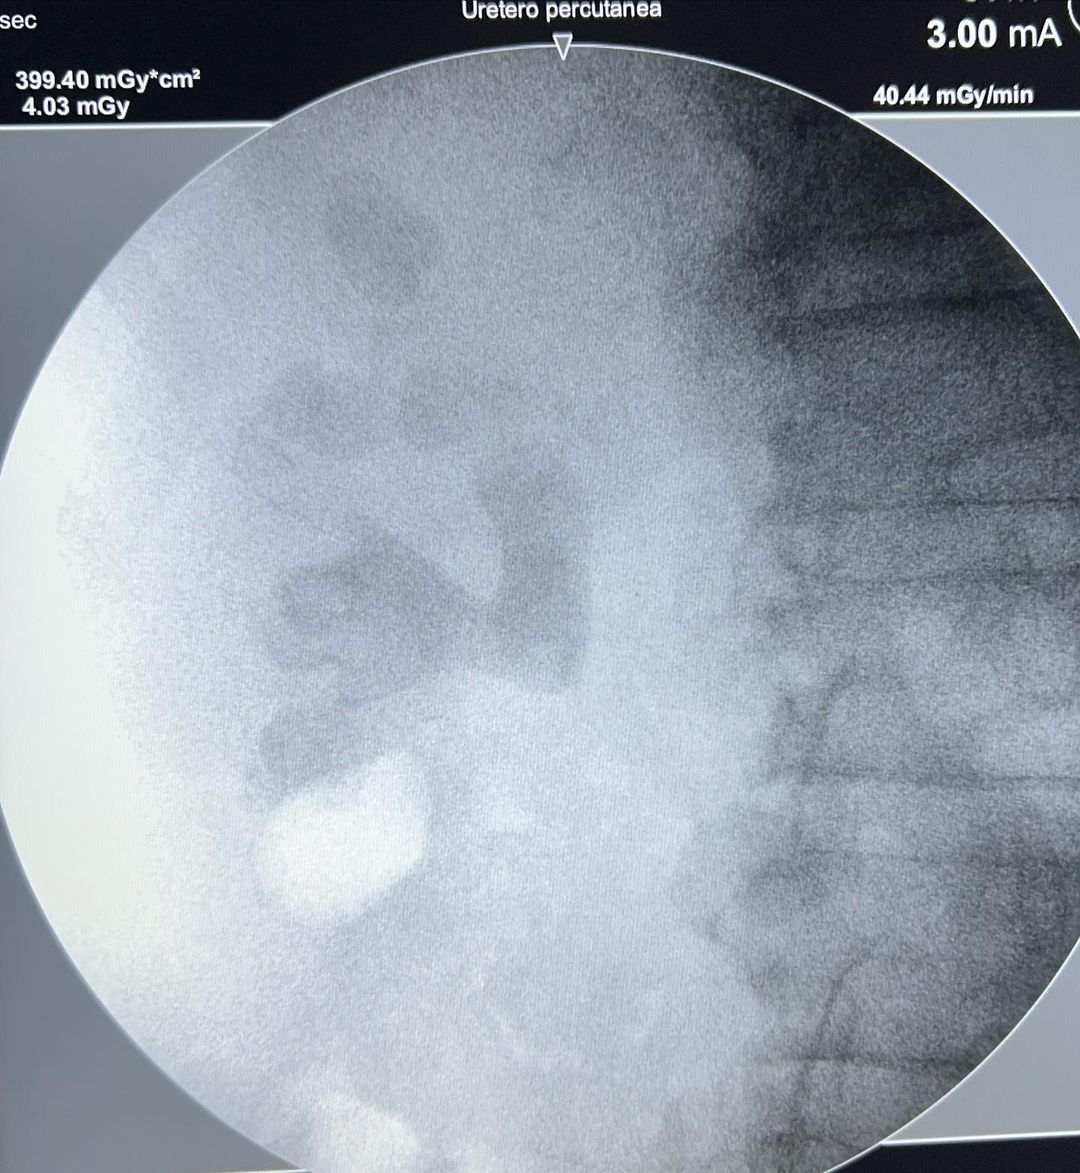

Especialista em Cirurgias Urológicas Minimamente Invasivas, com destaque para Cálculos Renais e Tumores Urológicos.

Imagens